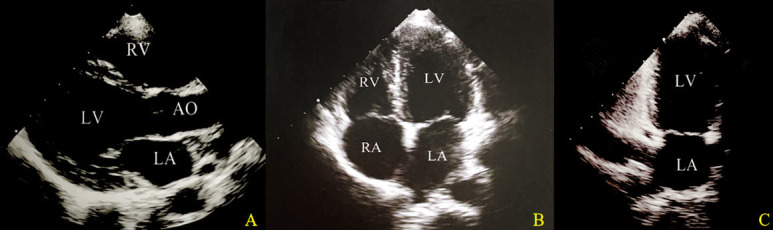

Objective: To investigate the two-dimensional speckle-tracking echocardiography (2D-STE) parameters associated with early impaired left ventricular systolic function in SLE patients and to estimate the potential clinical factors that may trigger and influence left ventricular systolic dysfunction.

Methods: This study collected a total of 36 patients admitted to the rheumatology and immunology department of Sun Yat-sen University between January 2020 and December 2021, who were newly diagnosed with SLE and had a Systemic Lupus Erythematosus Disease Activity Index 2000 Score≥4 points. An equal number of healthy controls matched for gender and age were included. All participants underwent routine echocardiography and two-dimensional speckle-tracking echocardiography (2D-STE) examinations. Various clinical data were also collected. Machine learning and regressions were used to estimate potential risk factors for left ventricular systolic dysfunction in SLE patients.